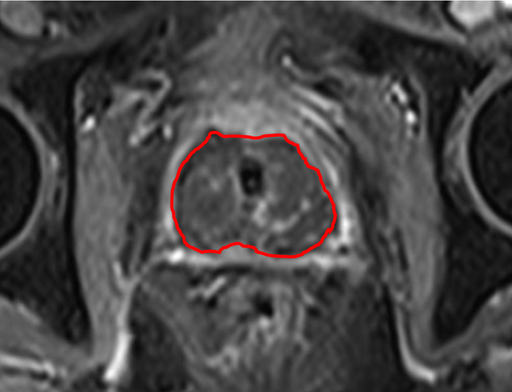

MR-bilder

Bild 1 visar effekten av behandlingen hos patient 9. Det mörka området som indikerar god behandlingseffekt täcker i detta fall hela prostatakörteln.